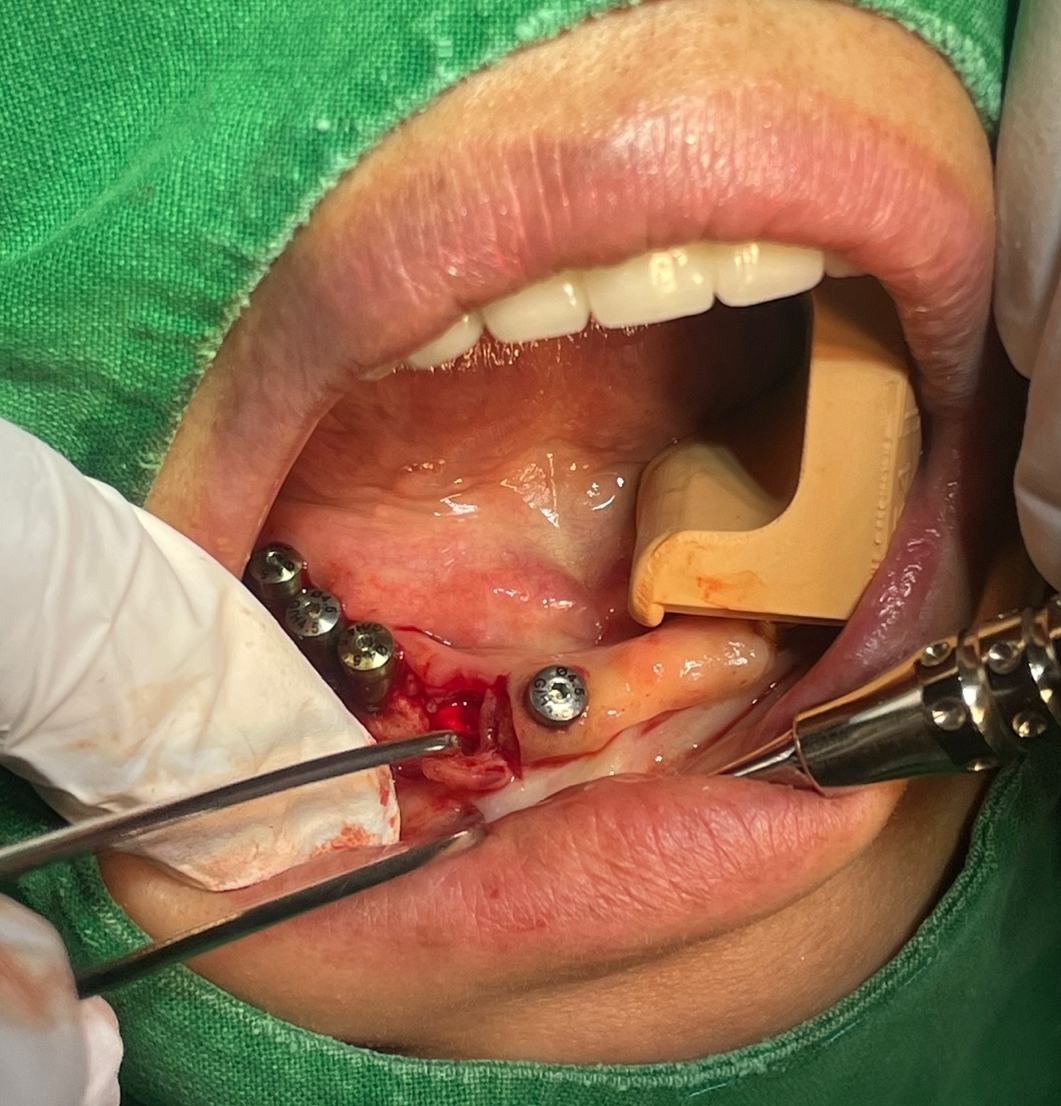

오늘 제가 수술한 환자분은 기존 타치과에서 쓰시던 임플란트 고정성 틀니의 만족도도 나쁘지 않았으나 나이가 아직 50대 후반으로 한창이신 여성 환자분이라 심미적인 이유로 고정성 치아를 원하셨고

제가 CT를 찍고 환자분께 일주일만 시간을 주시면 일주일뒤에는 예쁜 고정성 치아로 만들어 드린다고 자신있게 약속을 드린 환자분이었습니다.

심지어 임플란트를 단 4개만 심더라도 고정성으로 해드릴려고 노력하고 있습니다. 환자분이 느끼시는 만족도가 너무 차이가 납니다. 예전에는 교합력만으로 그 만족도를 가늠할려고 하였지만 그 와는 별개로 틀니를 빼고 있는 밤시간에 느끼는 무치악 스트레스도 무시 못하는 요인이라고 생각이 됩니다.

당장 비용 문제로 크게 고민 되시는 분이 아니라면 웬만하면 하악에서는 특히 고정성 치료를 권해 드리고 있습니다. 그리고 비용도 아예 일정금액으로 고정 시키고 심는 갯수는 제가 최대한 많이 식립해 드릴려고 하고 있습니다.

하악 무치악 환자분께는 어떠한 형태의 고정성 보철물의 디자인이 가능합니다.